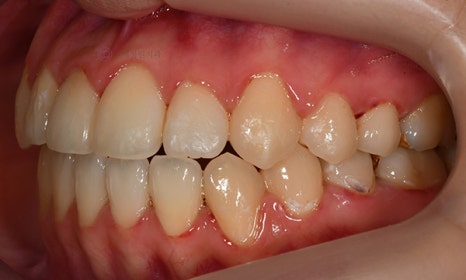

다음 케이스 역시 위 아래 중심선의 차이가 있어서 비대칭이 있어 보이는 케이스입니다. 중심선의 차이 뿐 아니라 앞니 및 어금니 부위에 거꾸로 물리는 반대교합이 관찰되고 있었습니다(원래는 위 치아가 아래 치아를 덮는 것이 정상적인 교합이나, 반대교합이란 위 치아가 아래 치아보다 더 안쪽으로 들어가서 물리는 교합을 말합니다).

2020.2

얼굴의 중심선과 위 치아의 중심선은 일치하여, 오른쪽 아래 작은 어금니를 발치하여 그 공간으로 아래 치열을 이동시켜줌으로써 중심선 및 교합을 개선하였습니다.

2021.2